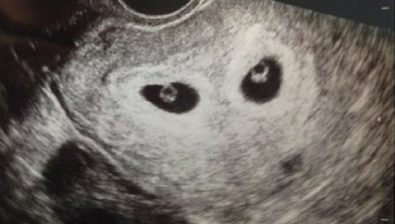

6 Weeks Pregnant: With Twins

Carrying multiples always presents a unique set of concerns for new mothers.

At week 6, it’s unlikely you know how many babies are actually inside of you, but your twin family history is often a good indication.

During your prenatal appointment on week 8, your doctor will be able to tell if you are carrying multiples or a single baby.